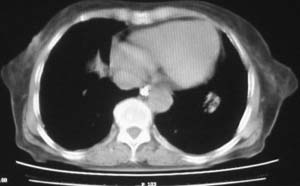

女,78岁,声嘶月余,否认有既往病史,有粉尘接触史10年。

符合矽肺,另外甲状腺可见病变,需强化明确.

双上肺结节融合影,周围有纤维条索影,结合粉尘接触史,首先考虑尘肺。双侧颈部有增大淋巴结,有声嘶表现,肺癌淋巴结转移不能排除。可结合颈部淋巴结活检。